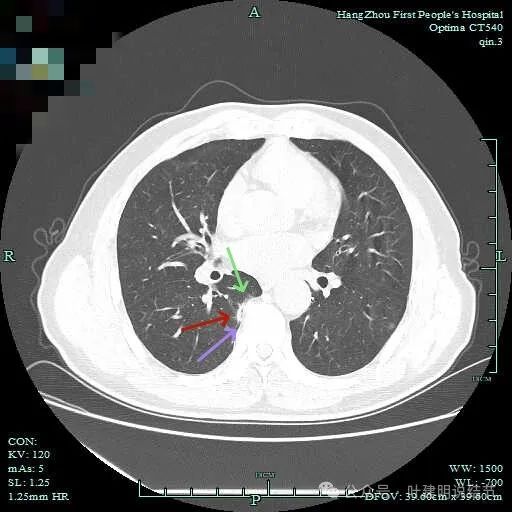

此层显得更呈小片状了。

与脊柱间似乎有间隙在,另见微小血管进入这条索状的偏高密度影处。

有细小血管进入,但说不上异常增粗。病灶仍是小片状,条状。

磨玻璃成分密度淡且界欠清,整体就是条索状弯曲的。

上图见细毛刺明显。